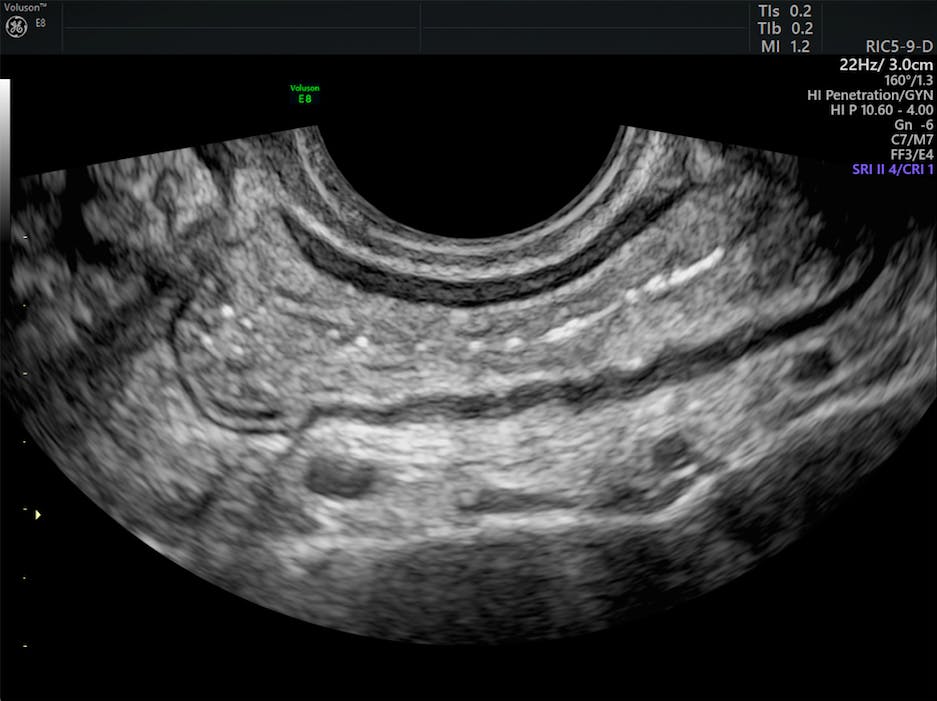

( A ) Transvaginal ultrasound image showing endometriosis ...

( A ) Transvaginal ultrasound image showing endometriosis ... from www.researchgate.net